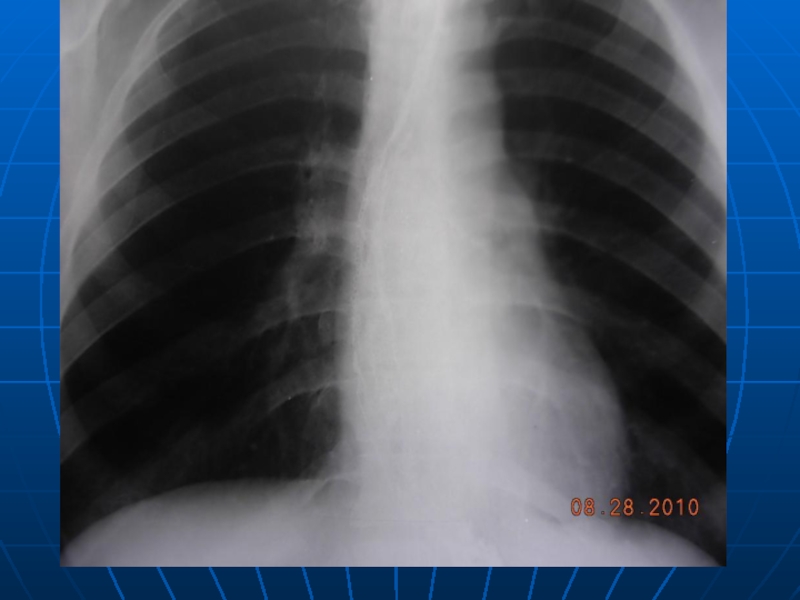

8. Кардиоспазм, ахалазия кардии